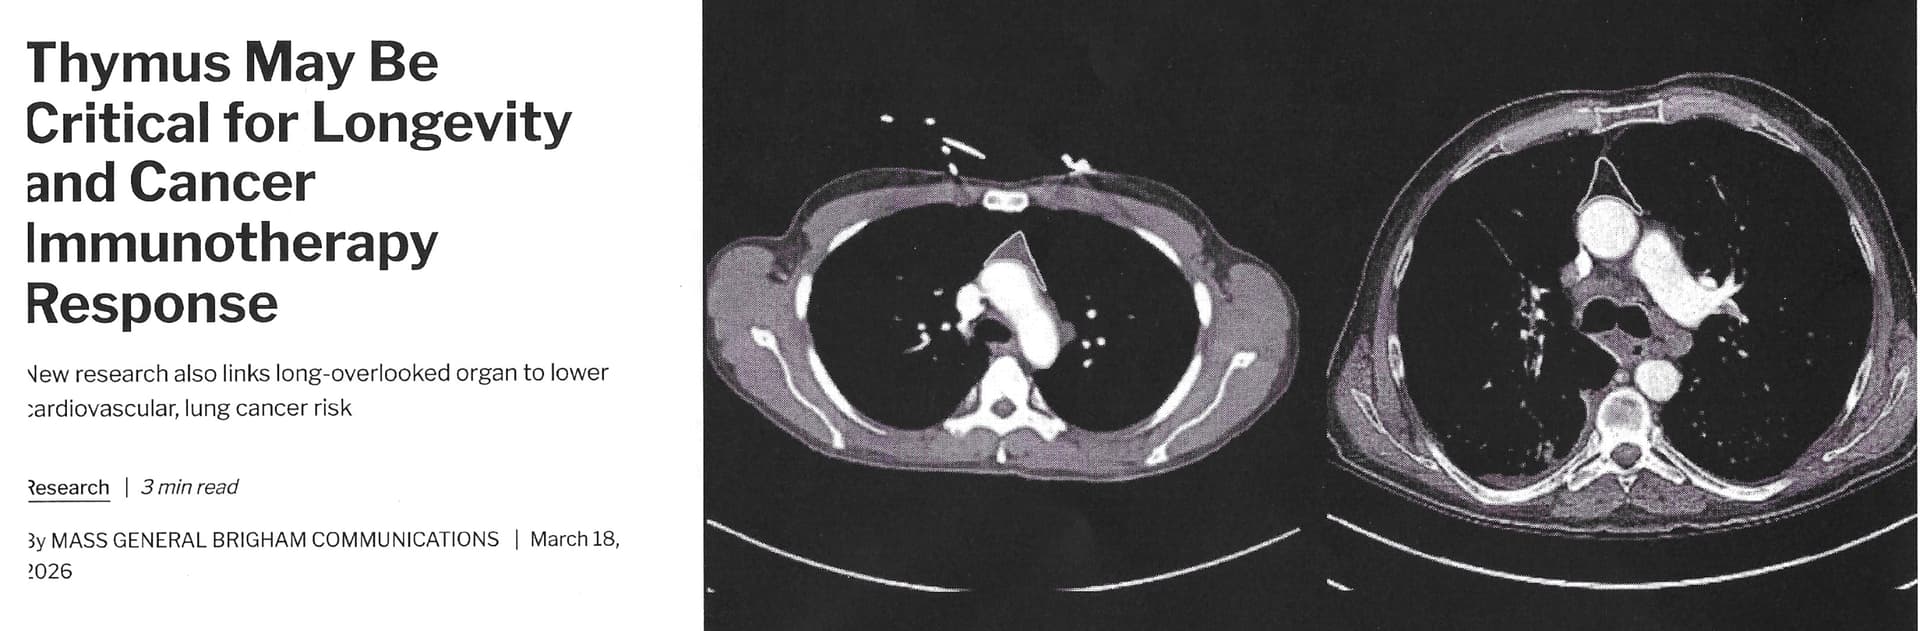

Then, this timely article came out: Long Dismissed in Adult Health, the Thymus May Be Critical for Longevity and Cancer Treatment | Mass General Brigham

Let’s compare a healthy thymus on the left image in the article to a less healthy thymus on the right.